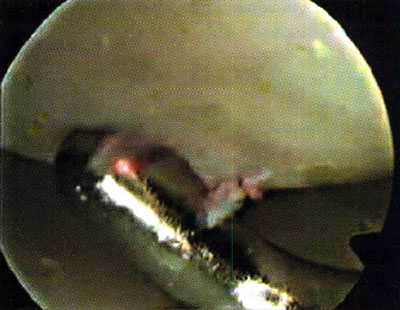

En 5 casos se comprobó, lesión condral tipo 1 de Noyes y Stabler (10), con una zona reblandecida a la palpación que nos orientó la exploración, diagnóstico y drenaje hemático con el palpador. En ningún caso la zona fue mayor de 20 mm de diámetro. Al realizar la punción con el palpador, se evacuó sangre roja fresca con la sensación de caer en una zona cavitaria. No se observó en ningún caso abombamiento de la zona reblandecida. En todos los casos, una sola perforación nos pareció suficiente.

Todas las lesiones correspondieron a la zona de apoyo no protegida por el menisco.

Al inicio de nuestra experiencia, nos llamó la atención, el hallazgo casual de este tipo de lesiones, en aquellos pacientes a los cuales se realizó la exploración artroscópica, convencidos de encontrarnos ante algún tipo de lesión meniscal del compartimiento interno y nos encontramos con meniscos sanos y cartílago aparentemente sano o con leve condritis tipo 1 en la zona de apoyo, a las cuales al realizar la palpación con el probador, el mismo penetraba con facilidad hasta llegar al hueso con la sensación de penetración en una cavidad y la salida de sangre roja rutilante de la misma.